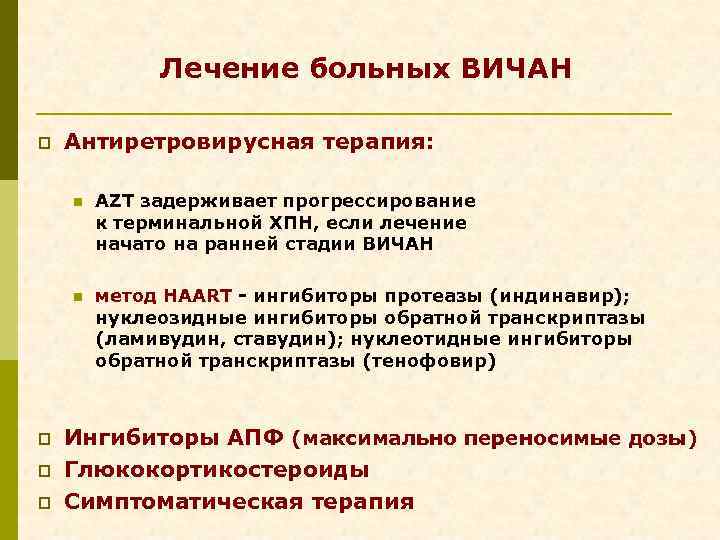

Лечение больных ВИЧАН p Антиретровирусная терапия: n n p p p AZT задерживает прогрессирование к терминальной ХПН, если лечение начато на ранней стадии ВИЧАН метод HAART - ингибиторы протеазы (индинавир); нуклеозидные ингибиторы обратной транскриптазы (ламивудин, ставудин); нуклеотидные ингибиторы обратной транскриптазы (тенофовир) Ингибиторы АПФ (максимально переносимые дозы) Глюкокортикостероиды Симптоматическая терапия